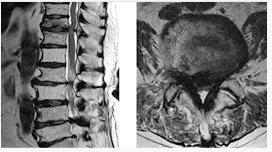

척추관 협착증의 방사선 소견